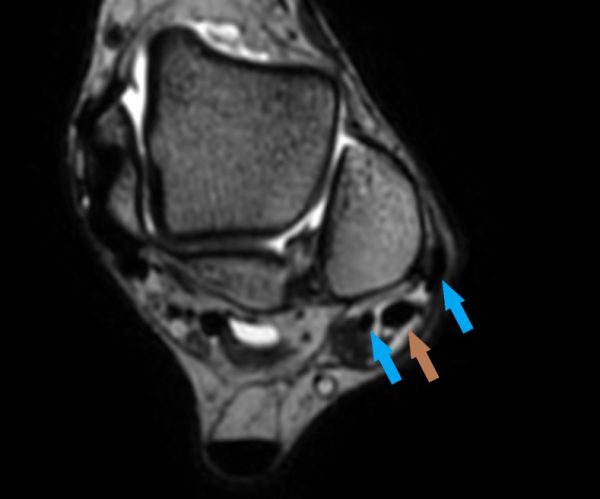

Home Schwerpunkte Krankheitsbilder Luxation der Peronealsehnen Chronische Peronealsehnenluxation mit Tendon split der Peroneus brevis Sehne

Chronische Peronealsehnenluxation mit Tendon split der Peroneus brevis Sehne